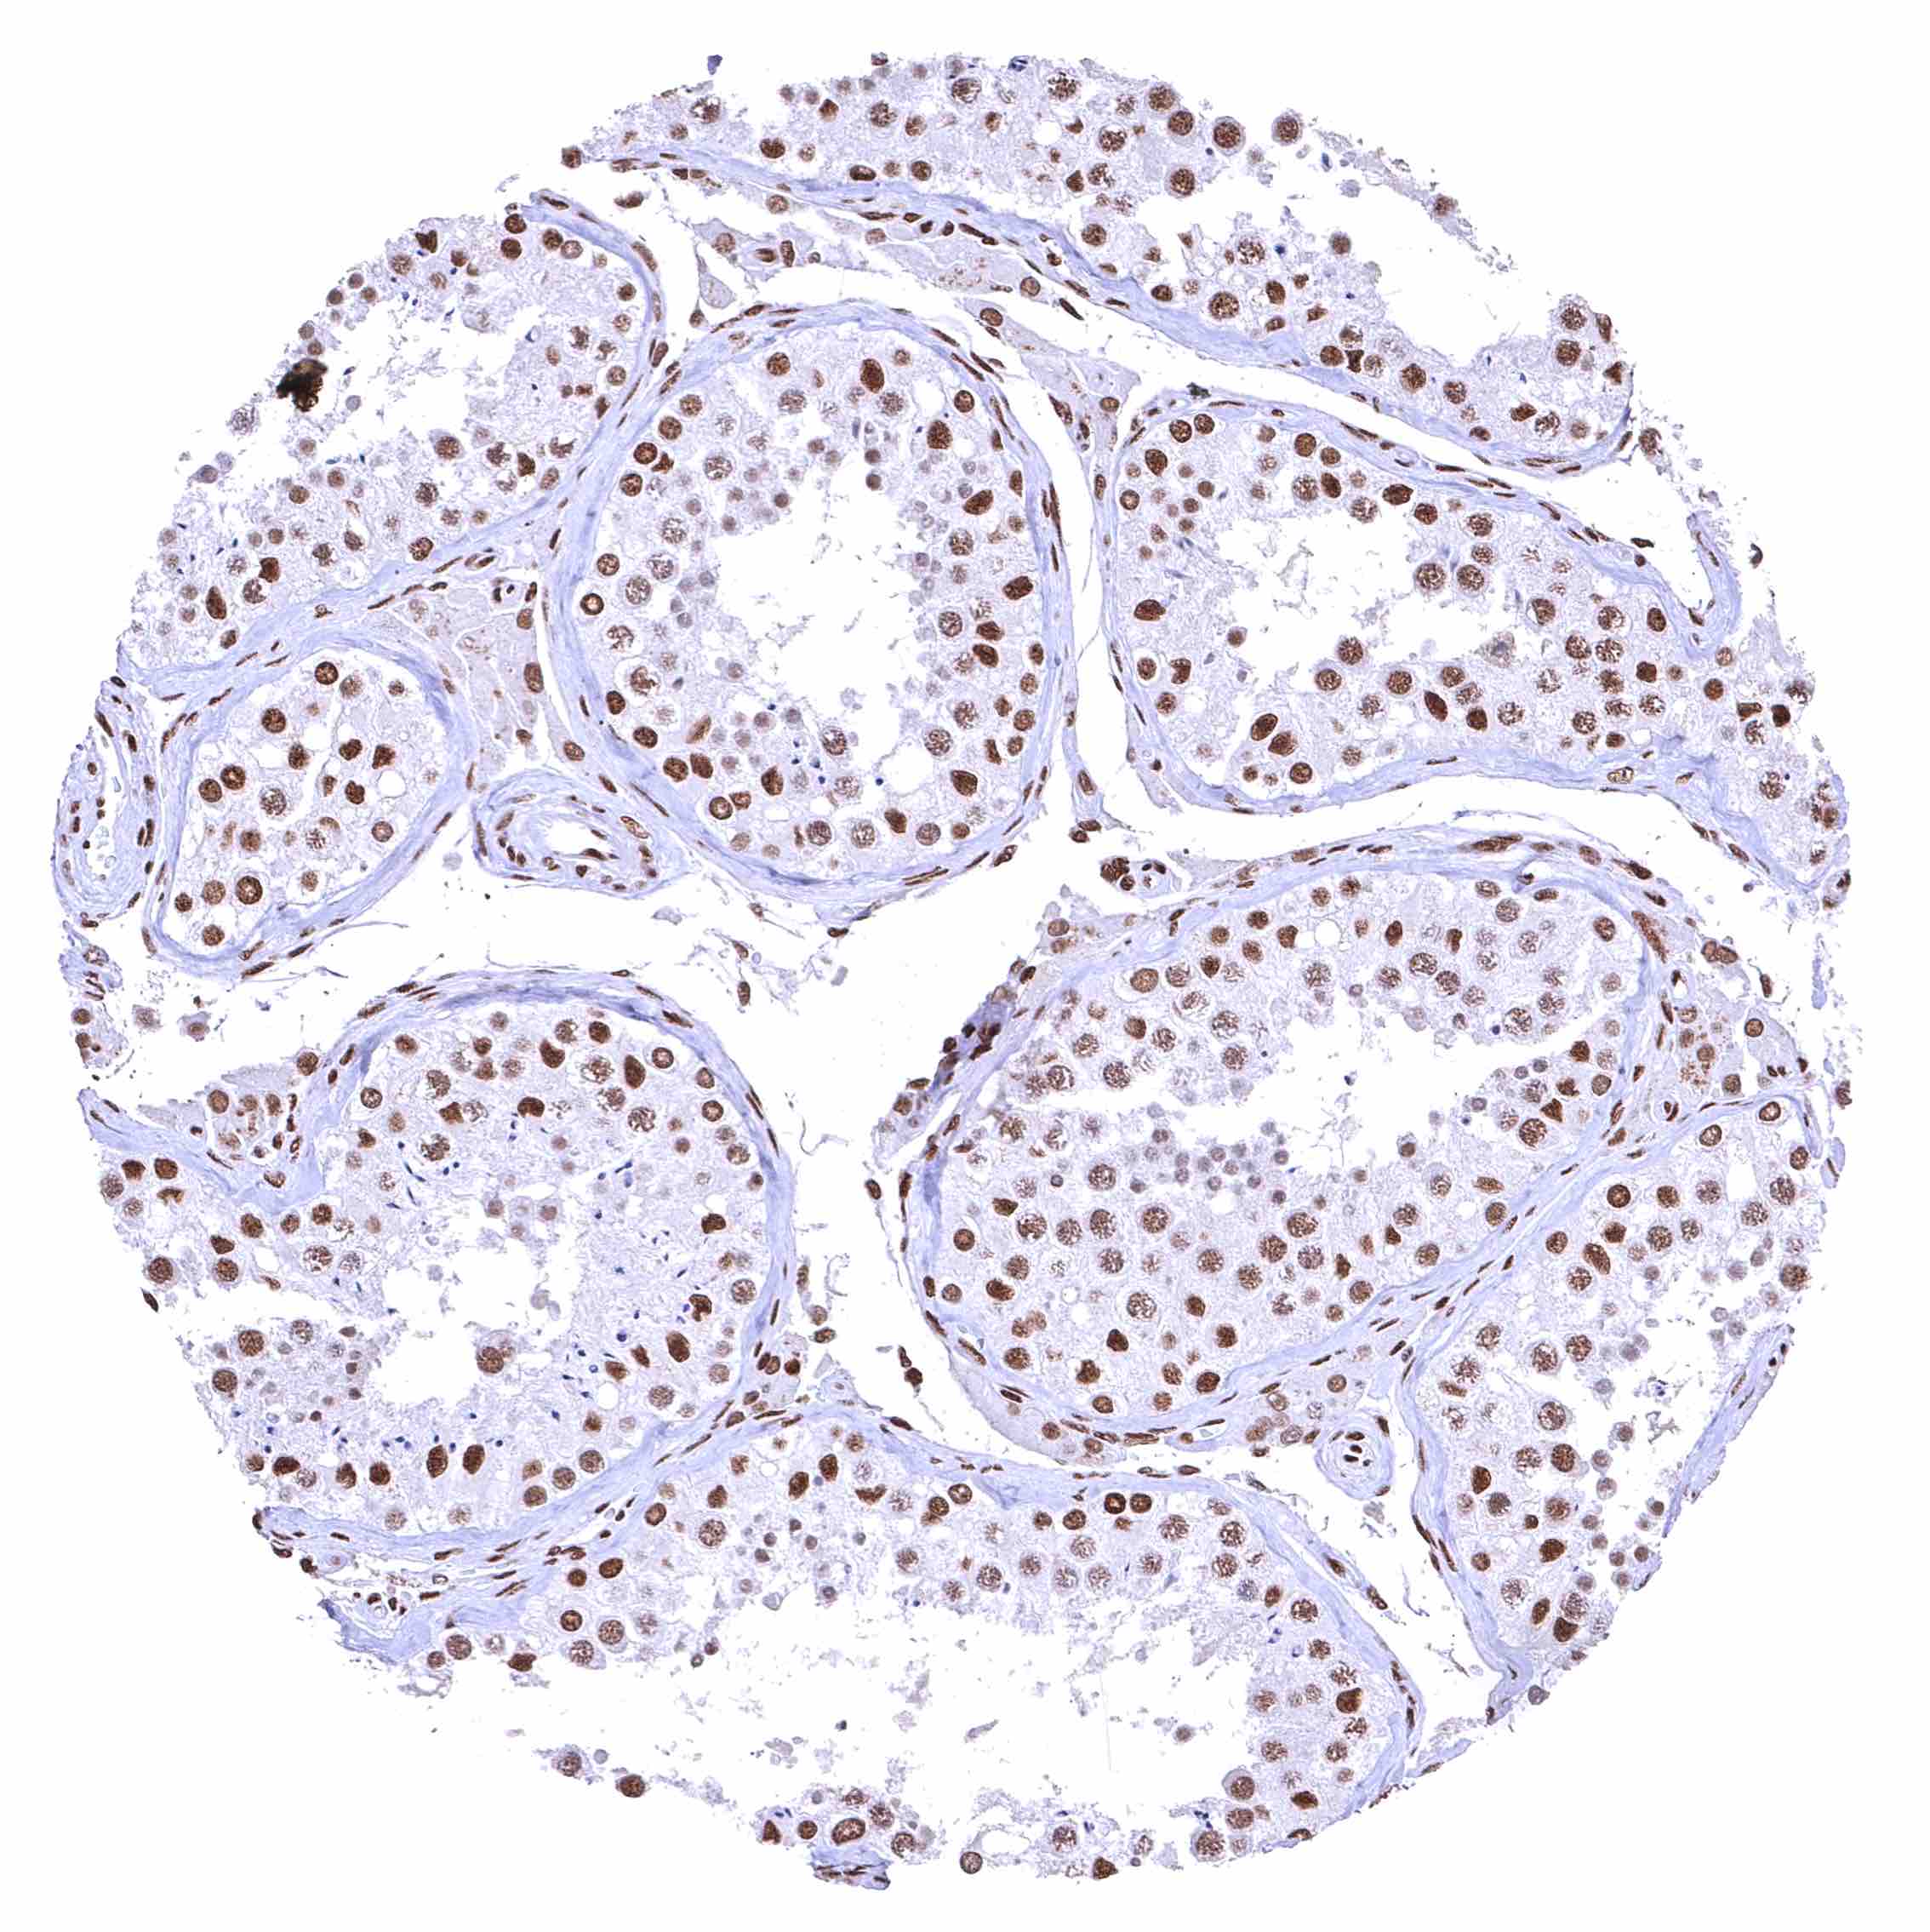

Testis – The level of nuclear BRD4 staining decreases with maturation of germ cells.